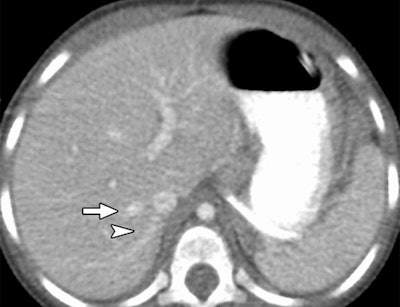

In an objective evaluation, reduced-dose MBIR images had decreased image noise compared with standard-dose 30% ASIR images (for example, 12.7 HU versus 19.4 HU in the aorta, respectively, and 8.7 HU versus 14.2 HU in the liver).

The MBIR images also had less noise (p > 0.004), and spatial resolution was superior overall for MBIR. The readers found MBIR images equivalent to standard-dose images for the lungs and soft tissues (p > 0.05) but inferior for bone imaging (p = 0.004), the group reported.

Image quality was also judged to be sharper with MBIR. Using the same reduced-dose acquisition, lesion detectability was better (32 of 84 rated lesions, 38%) or the same (52 of 84 rated lesions, 62%) with MBIR compared to 100% ASIR reconstruction.